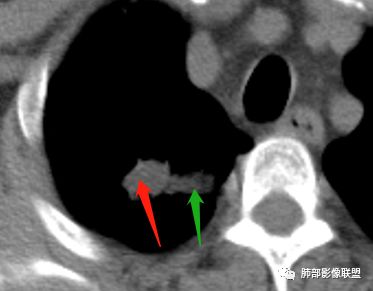

纵隔窗提示内侧部分密度不够实

边缘平直、凹陷为主,部分膨隆

内部小点状影提示可能支气管腔内粘液栓